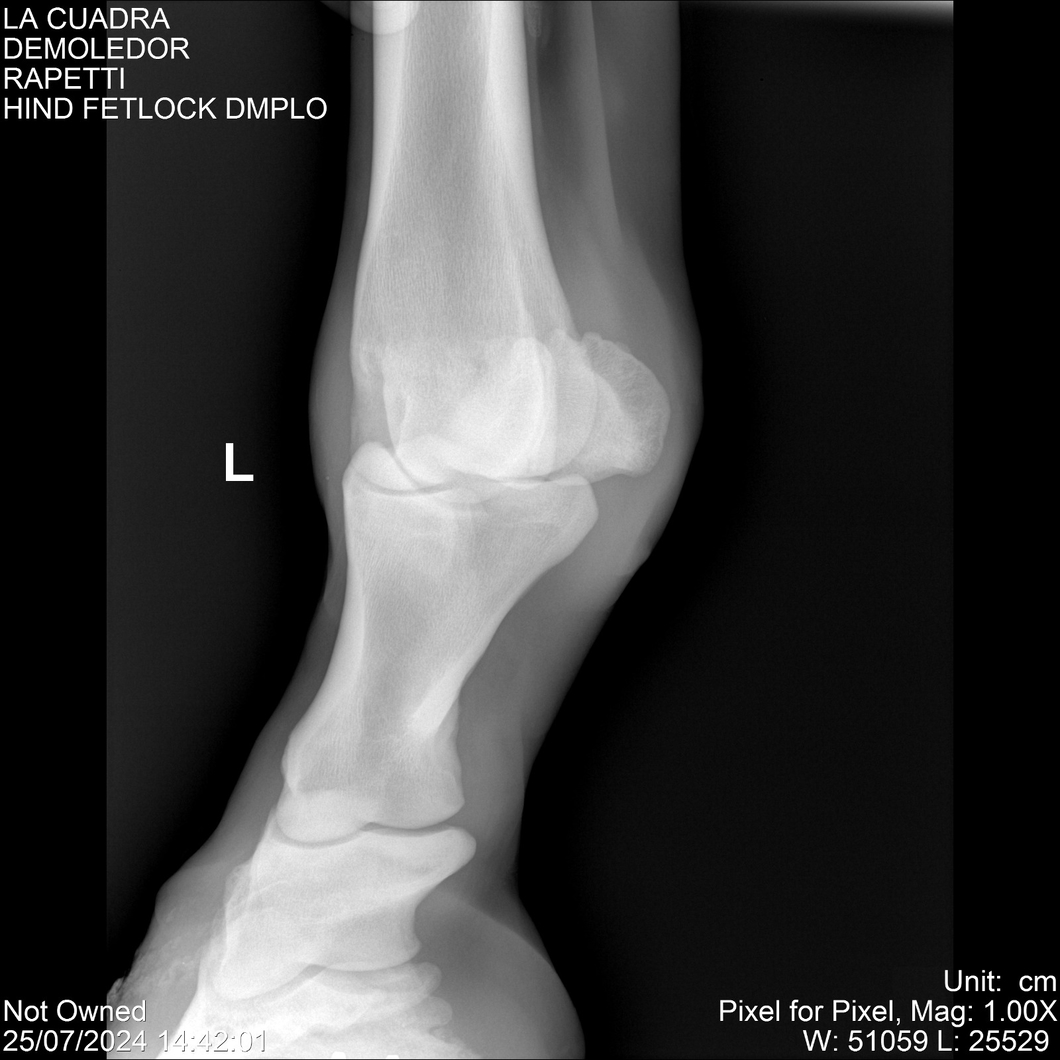

LOTE 14, DEMOLEDOR 🔥 🔥 🔥 Lote Anterior Volver al remate Lote Siguiente Ficha Contacto Montevideo - Ficha del Lote Identificador: #284454 Categoría: Yeguarizos Montevideo - 89 Visualizaciones ClicData Contacto Empresa: Abelenda N. R., Walter Hugo Nombre*: Teléfono* : E-mail* : Mensaje Enviar Registrese gratis Este contenido Exclusivo está disponible sólo para usuarios registrados Ingresar